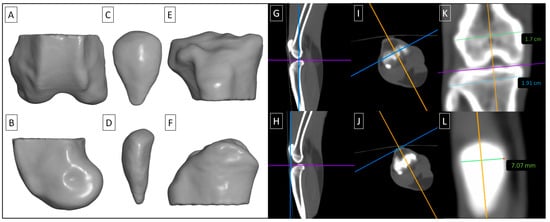

2.4.1. Quantification of Computed Tomography Images

2.4.2. Quantification of Computed Digital Absorptiometry Images